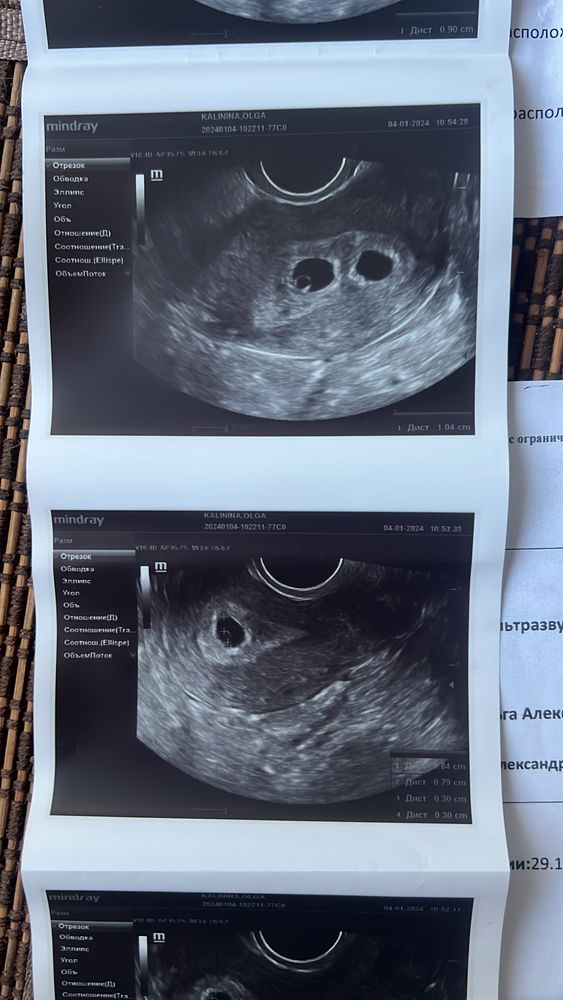

Сегодня была на узи, 21ДПП, увидели сначала одно ПЯ, затем я попросила получше пошурудить и але оп еще одно 🙈

перенос был 14.12 двух пятидневок)